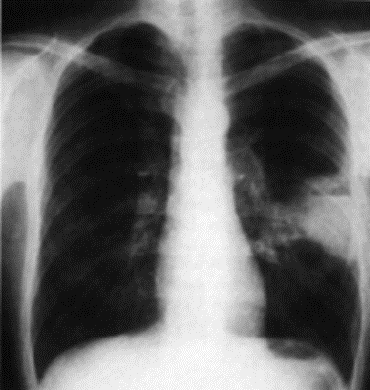

1.2.1 Radiografia (tomografia, broncografia)

Metodo diagnostico prevalente, eventualmente completato con tomogramma delle parti dubbiose o broncografia (a contrasto).